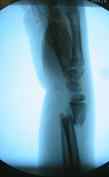

- first surgery